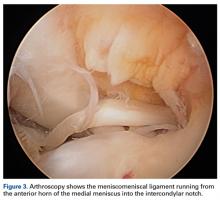

Arthroscopy of the left knee was performed for reconstruction of the ACL and repair of the menisci ( Figures 3, 4 ). The suprapatellar pouch and medial and lateral gutters were normal. There was grade 2 fraying of the distal portion of the trochlea medially and laterally in the medial facet of the patella. An aberrant anterior horn medial meniscus attachment was found; it had been interpreted as a tear on MRI. This aberrancy ran through the femoral intercondylar notch and attached to the posterior horn of the lateral meniscus ( Figures 5A-5H ) ( watch the video ).Discussion

The medial and lateral menisci typically are separate fibrocartilaginous structures acting as a cushion for the knee, but normal variant connections between the structures have been described. These connections include the anterior transverse meniscal ligament, the posterior transverse meniscal ligament, and the medial and lateral oblique meniscomeniscal ligaments. 3 In the present case, a medial oblique meniscomeniscal ligament was identified. Its path between menisci was traceable on coronal and axial views. Video taken during arthroscopy also clearly showed its path and its relationship to other structures in the knee. To Dr. Flanigan’s knowledge, this ligament was not previously described with video. It is important to distinguish this ligament from a horizontal tear of the meniscus, given the potential for misinterpretation on MRI. A horizontal tear is a degenerative change that often occurs in older patients. Our patient was 18 years old at time of injury. In addition, the surface of his lower meniscus was smooth, whereas in a tear the edge is irregular and discontinuous. Dr. Flanigan prefers to leave this ligament intact unless resection would provide better visualization during arthroscopy. His reasoning is that the functional characteristics of the ligament are not well understood.